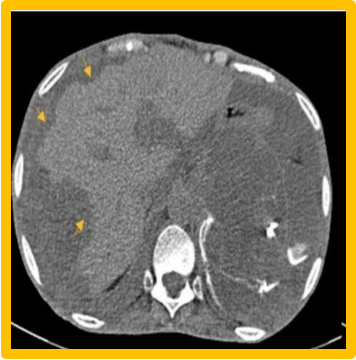

- US, CT

- U/S, CT- scalloped indentation help diagnosis.